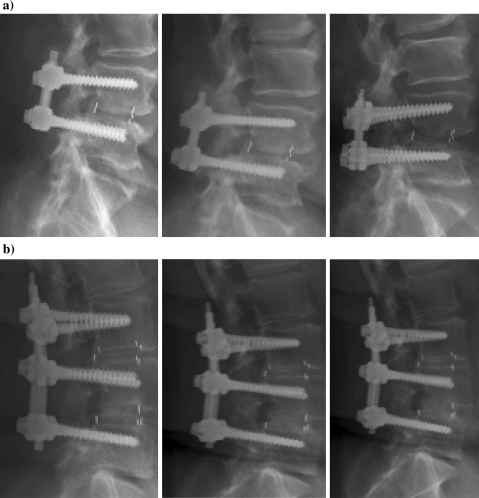

Despite the fact that none of the patients in this study was clinically symptomatic, evidence of vertebral endplate osteoclastic activity was demonstrated radiographically in all 17 patients in 3 months following surgical intervention (Fig. 2). Radiographic evidence of fusion was apparent in all patients at 6 months (Fig. 3). Ossification of the decalcified areas of the vertebrae was evident in all patients at the 6-month assessment and seen at all subsequent examinations.

Fig. 3.

Include case reports and X-rays at 6 months for (a) Patient 1 (79-year-old male) and (b) Patient 2 (67-year-old female. Develop figure to show progressive change at each time point that was assessed. Goal of figure is to show continuity in assessment and comparability in the technique of the assessment. a 79-year old male at 6, 12, and 24 b. 67-year-old female at 6, 12, and 24 months